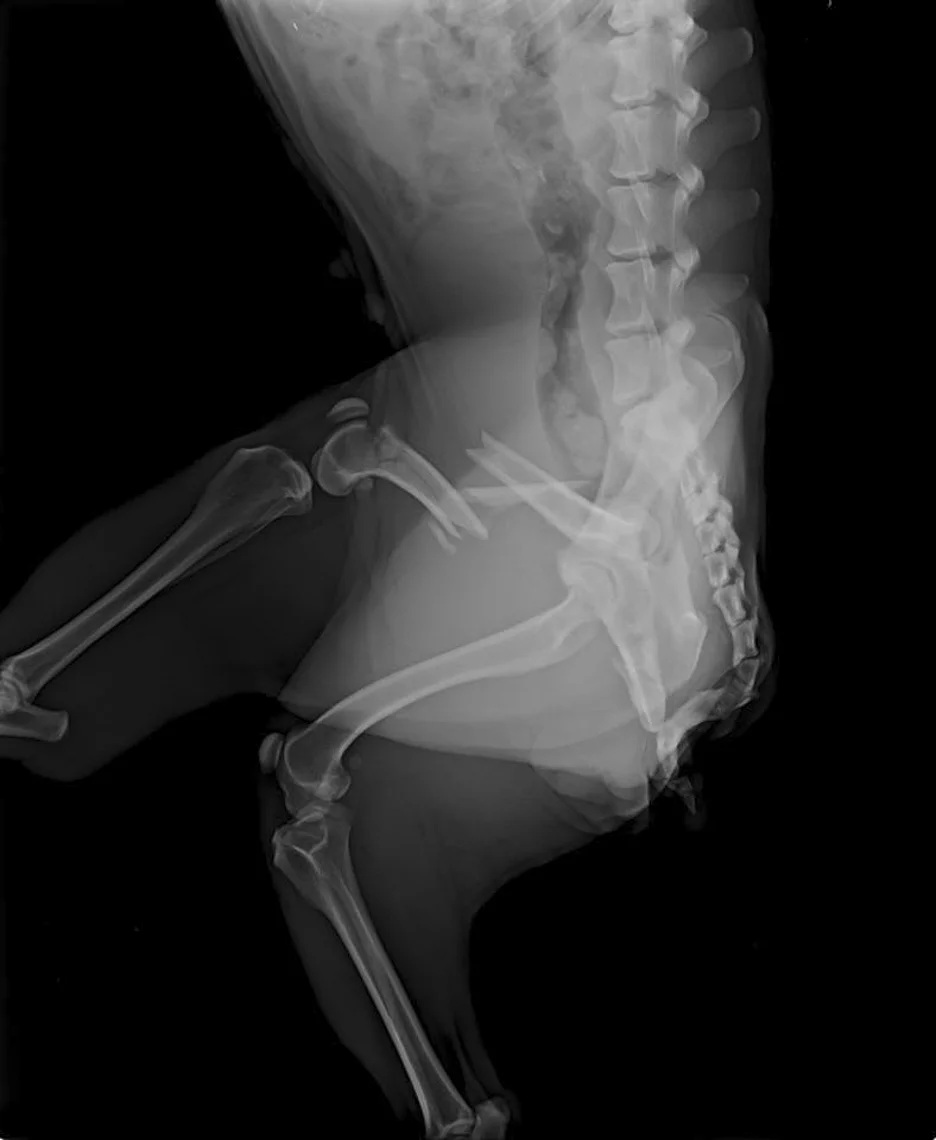

Reptar: Snapped, broken right femur, Upper respiratory infection, Emaciated, Entropion, Heart murmur, Heartworm negative

Per Paige, “And Robyn, it’s the worst case we’ve seen all year..”

Reptar video showing injury: